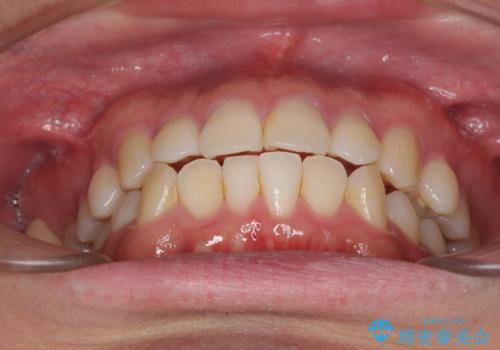

インビザラインで奥歯の咬み合わせと前歯のデコボコを改善

- 前歯のデコボコと奥歯の咬み合わせを気にして来院された患者様です。

前歯のデコボコはインビザラインで十分に対応可能と判断できましたが、咬合力が強いため、臼歯(特に右側)の交叉咬合はインビザライン単体では困難と思われました。

インビザライン単体では右側の交叉咬合を解消することができなかったため、アンカースクリューを併用して咬合を改善させました。